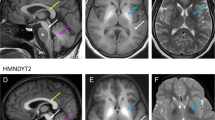

Hypermanganesaemia with dystonia 1 (HMNDYT1) caused by biallelic mutations in SLC30A10 was the first inherited manganese transporter defect described. Impaired biliary excretion leads to accumulation of manganese in the liver and brain, resulting in liver disease and generalised dystonia. Manganese deposition in the brain causes characteristic neurodegenerative features including severe neuronal loss in the globus pallidus and a vacuolated myelinopathy. MRI brain appearances are pathognomonic with hyperintensity on T1-weighted images of the globus pallidus and striatum, and the white matter of the cerebrum and cerebellum, midbrain, dorsal pons and medulla, while the ventral pons is typically spared (Fig. 38.1a, b). T2-weighted images show corresponding hypointensity of the globus pallidus and striatum (Fig. 38.1c). Activation of erythropoietin gene expression due to excess manganese leads to polycythaemia, which often precedes clinical symptoms. Whole blood manganese levels are significantly raised and usually exceed 1000 nmol/L. Another characteristic is a depletion of iron stores with increased total iron-binding capacity and low ferritin values. Some patients develop hypothyroidism, which is consistent with findings in SLC30A10 knockout mice (Hutchens et al. 2017). Disease onset is usually within the first few years of life with progressive, generalised dystonia; however, cases of adult-onset atypical Parkinson’s disease have been described. Some patients have also presented with primary hypotonia or spastic paraplegia (Gospe Jr. et al. 2000; Gulab et al. 2018; Zaki et al. 2018). Manganese chelation with intravenous disodium calcium edetate, in combination with iron supplementation to reduce the uptake of manganese, reduces manganese blood and tissue levels, improves neurological symptoms and halts liver disease progression (Tuschl et al. 2012, 1993; Quadri et al. 2012, 2015).

Characteristic MRI brain appearances due to manganese overload in SLC30A10 (HMNDYT1) and SLC39A14 (HMNDYT2) transporter defects (Tuschl et al. 2016). (a, b) T1-weighted MR imaging shows hyperintensity of the globus pallidus and striatum (blue arrow), and the white matter in the cerebrum, cerebellum, midbrain, dorsal pons (white arrows) with a pathognomonic sparing of the ventral pons (red star). (c) T2-weighted MR imaging shows corresponding hypointensity of the globus pallidus and striatum (blue arrow)

Biallelic mutations in SLC39A14 cause hypermanganesaemia with dystonia 2 (HMNDYT2) due to impaired uptake of manganese into the liver for subsequent biliary excretion. Manganese accumulates in extrahepatic tissues, causing an isolated neurological phenotype of rapidly progressive Parkinsonism-dystonia with onset in infancy or childhood. Whole blood manganese levels are highly raised and MRI brain appearances are identical to that of HMNDYT1 (Fig. 38.1). Hypointensity of the globus pallidus and striatum on T2-weighted images is often pronounced and may be mistaken as the eye of the tiger sign observed in neurodegeneration with brain iron accumulation (NBIA) disorder. Chelation therapy with disodium calcium edetate has been used with some success; however, clinical response is poor in most patients, most likely due to advanced disease progression and significant degree of neurodegeneration (Tuschl et al. 2016, 1993; Zeglam et al. 2018).